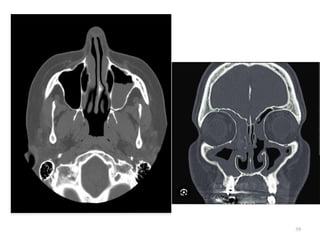

ACUTE SINUSITIS CHRONIC SINUSITIS

The use of CT should be reserved for patients who (1) Present with severe unilateral maxillary

pain, facial swelling, and fever (2) Have not responded to antibiotic therapy

RADIOLOGICAL INVESTIGATIONS

• CT Scan

• MRI